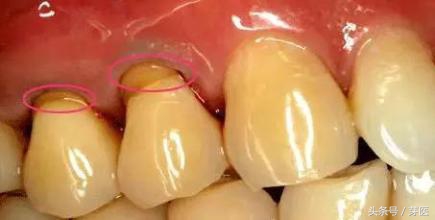

在口腔科,有种牙病名叫楔状缺损,医学解释是牙齿唇颊侧颈部硬组织发生缓慢消耗所致的缺损,由于这种缺损常呈楔形而得名。

楔状缺损

有点听不懂?简单点说,就是牙齿靠近牙龈的部分,出现了横沟,从侧面看像是楔形。由于牙釉质被破坏,俗称“漏神经”了,所以一遇到冷热酸甜的刺激就会疼痛,严重时还会发生剧烈的牙痛,而造成楔状缺损,最多的原因就是天天用力横刷牙!所以,楔状缺损也叫刷牙磨损。